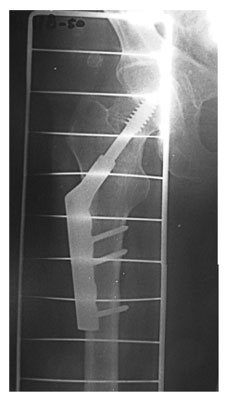

- Консолидированный стабильный чрезвертельный перелом правого бедра

Консолидированный стабильный чрезвертельный перелом правого бедра